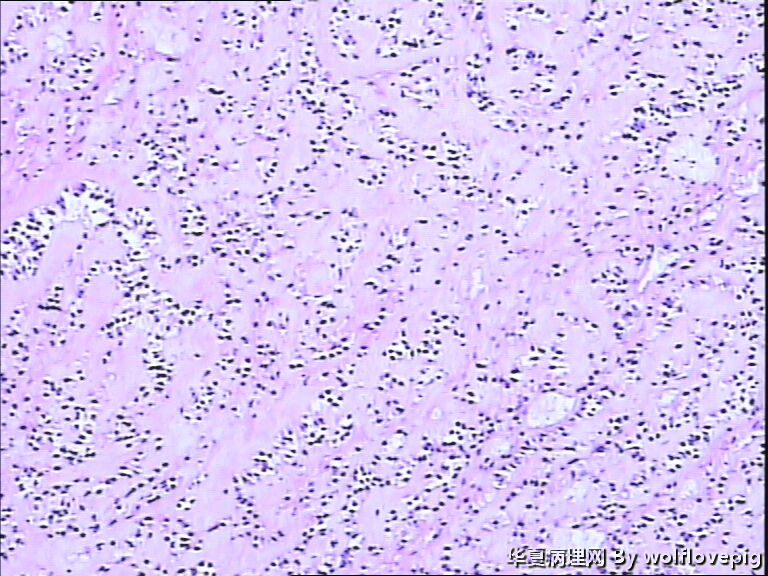

求助!肌瘤变性?

• 求助!肌瘤变性?图2

图2

平滑肌瘤伴间质玻璃样变性,像是冰冻的片子吧?》

上皮样平滑肌瘤,鉴别PECOMA

像平滑肌瘤玻璃变性

平滑肌瘤

上皮样平滑肌瘤

符合平滑肌瘤伴梗死,多取材寻找有无质软,肉质样变区,破碎的组织最麻烦,要慎重。